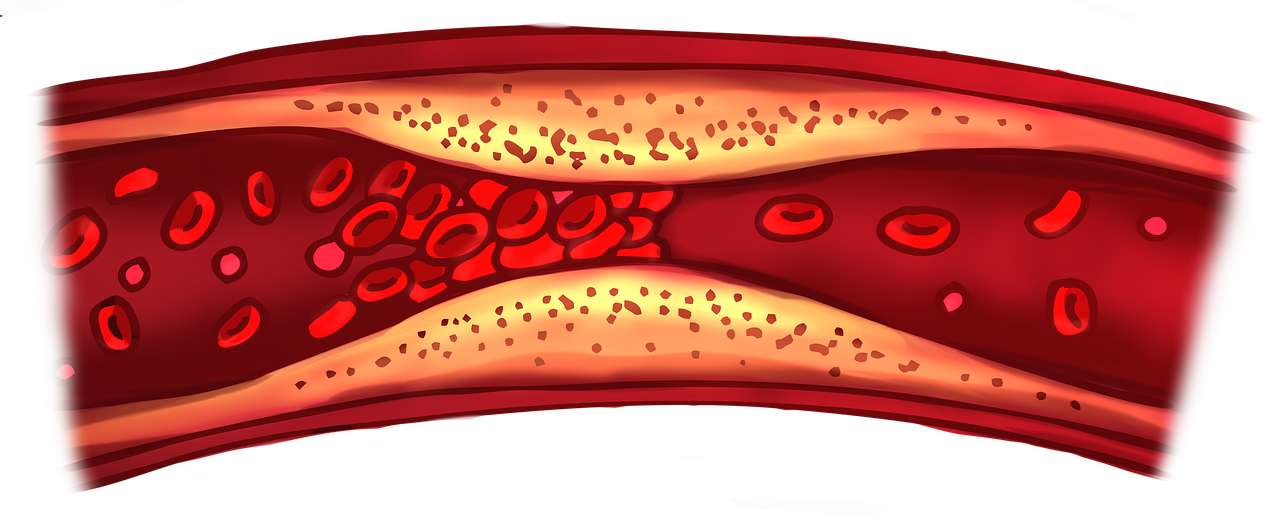

경동맥 초음파: 목 혈관의 이상 탐지

경동맥 초음파는 목 부위의 경동맥을 초음파로 검사하여 혈관의 협착이나 플라크 존재 여부를 확인합니다. 경동맥의 이상은 뇌혈류에 직접적인 영향을 미쳐 뇌출혈의 위험 요인이 될 수 있습니다. 이 검사는 비침습적이며 통증이 없고, 비교적 짧은 시간 내에 결과를 얻을 수 있어 예방적 검사로도 활용됩니다.